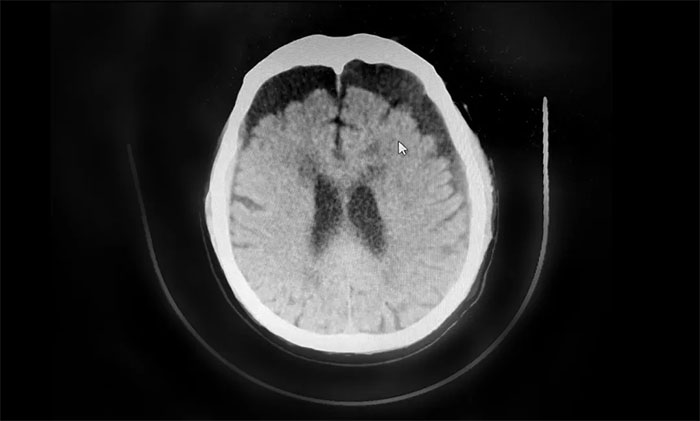

行颅脑CT检查,患者双侧额颞枕顶部可见硬膜下积液血肿,双侧额叶受压明显,不排除积液血肿进一步加重。若不及时手术治疗,病情可能进一步恶化,甚至可能危及生命。

▲ 患者双侧额顶部硬膜下积液血肿明显